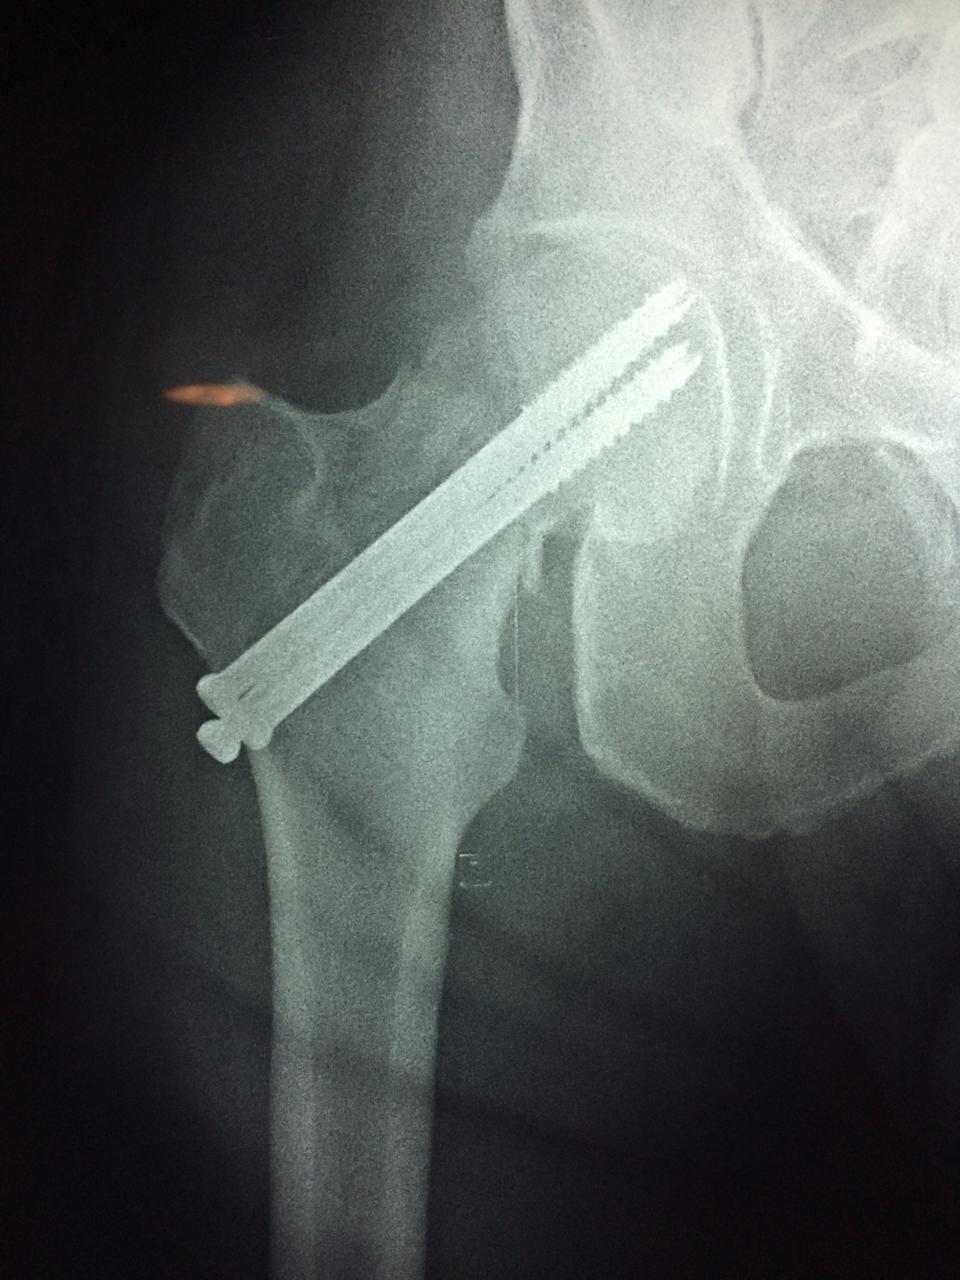

La cirugía de fractura de cadera se realiza para reparar una ruptura en la parte superior del hueso del muslo. Este hueso se denomina fémur.

A menudo se recomienda la cirugía para reparar la fractura debido a dichos riesgos.